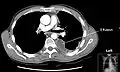

Chest computed tomography is more accurate for diagnosis and may be obtained to better characterize the presence, size, and characteristics of a pleural effusion. Lung ultrasound, nearly as accurate as CT and more accurate than chest X-ray, is increasingly being used at the point of care to diagnose pleural effusions, with the advantage that it is a safe, dynamic, and repeatable imaging modality.[15] To increase diagnostic accuracy of detection of pleural effusion sonographically, markers such as boomerang and VIP signs can be utilized.[16]

A pleural effusion is usually diagnosed on the basis of medical history and physical exam, and confirmed by a chest X-ray. Once accumulated fluid is more than 300 mL, there are usually detectable clinical signs, such as decreased movement of the chest on the affected side, dullness to percussion over the fluid, diminished breath sounds on the affected side, decreased vocal resonance and fremitus (though this is an inconsistent and unreliable sign), and pleural friction rub. Above the effusion, where the lung is compressed, there may be bronchial breathing sounds and egophony. A large effusion there may cause tracheal deviation away from the effusion. A systematic review (2009) published as part of the Rational Clinical Examination Series in the Journal of the American Medical Association showed that dullness to conventional percussion was most accurate for diagnosing pleural effusion (summary positive likelihood ratio, 8.7; 95% confidence interval, 2.2–33.8), while the absence of reduced tactile vocal fremitus made pleural effusion less likely (negative likelihood ratio, 0.21; 95% confidence interval, 0.12–0.37).[11]

A pleural effusion appears as an area of whiteness on a standard posteroanterior chest X-ray.[12] Normally, the space between the visceral pleura and the parietal pleura cannot be seen. A pleural effusion infiltrates the space between these layers. Because the pleural effusion has a density similar to water, it can be seen on radiographs. Since the effusion has greater density than the rest of the lung, it gravitates towards the lower portions of the pleural cavity. The pleural effusion behaves according to basic fluid dynamics, conforming to the shape of pleural space, which is determined by the lung and chest wall. If the pleural space contains both air and fluid, then an air-fluid level that is horizontal will be present, instead of conforming to the lung space.[13] Chest radiographs in the lateral decubitus position (with the patient lying on the side of the pleural effusion) are more sensitive and can detect as little as 50 mL of fluid. Between 250 and 600mL of fluid must be present before upright chest X-rays can detect a pleural effusion (e.g., blunted costophrenic angles).[14]